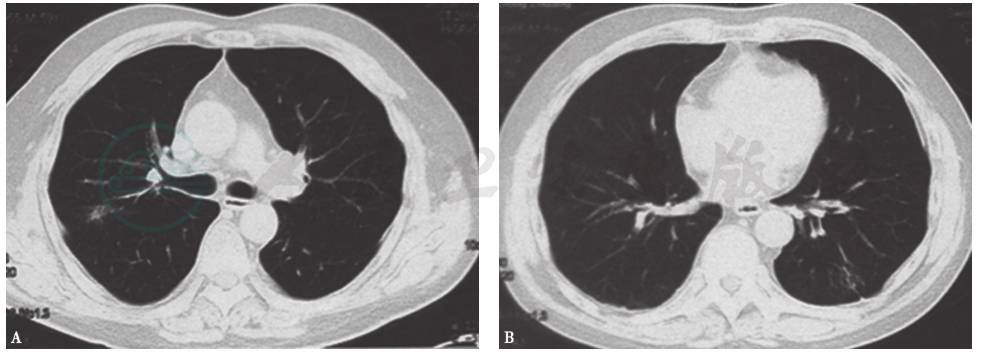

鉴于患者病情已有改善,予以甲泼尼龙治疗(20mg/d×4w,之后每周减2mg,至12mg/d时维持3个月,之后每2周减2mg,以4mg/d做维持量)。期间,于口服甲泼尼龙剂量为12mg/d时复查胸部CT,见双肺内阴影已基本吸收(图2);外周血IgG4水平为1310mg/L;患者无明显不适。

图2 复查胸部CT表现(2014-06-10)